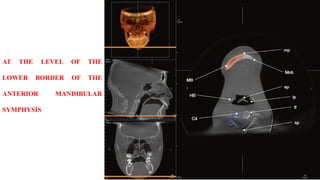

AT THE LEVEL OF THE

LOWER BORDER OF THE

ANTERIOR MANDIBULAR

SYMPHYSIS

AT THE LEVELOF THE LOWER BORDER OF THE ANTERIOR MANDIBULAR SYMPHYSIS